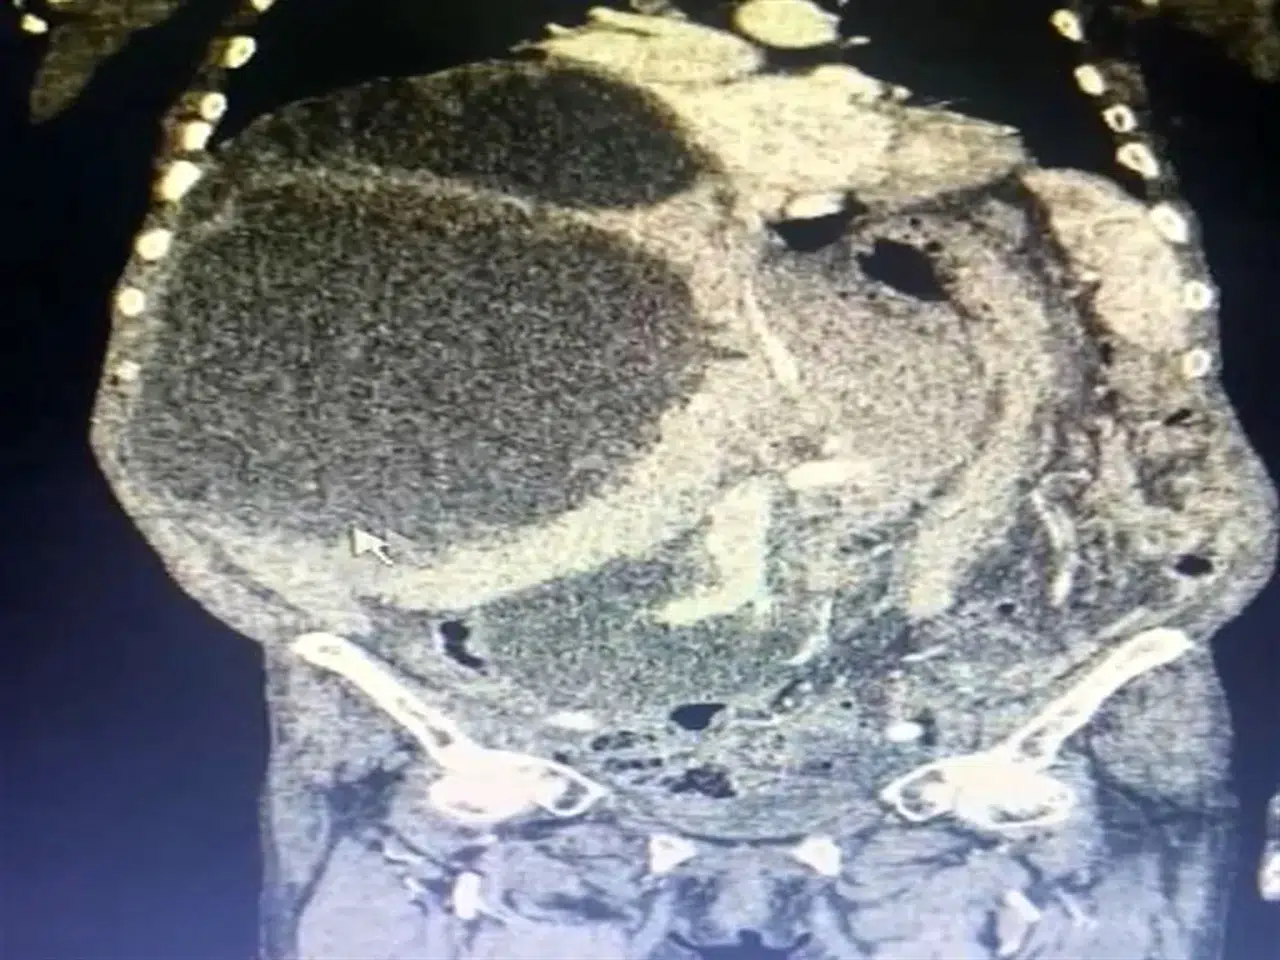

Karaciğerde 90 Santimetrelik Kedi-Köpek Kisti Başarıyla Alındı!

GÜMÜŞHANE’de Asiye Taşdelen’in (76), karnındaki şişlik ve ağrı şikayetiyle başvurduğu hastanede yapılan tetkikler sonucu karaciğerinde tespit edilen ve toplamda 90 santimetreye ulaşan 3 ayrı kedi-köpek kisti, gerçekleştirilen operasyonla çıkarıldı. Genel Cerrahi Uzmanı Operatör Dr. İsmet Çelik, kedi ve köpeklerle oluşan kistlerin insanlara bulaşma riskine ilişkin uyarılarda bulunarak, “Dünya literatüründe 90 santimetreye ulaşarak tüm karnı dolduran kist görmedik. Ameliyatımız 2 saat sürdü” dedi.

Çiftçilik yapan Asiye Taşdelen karnındaki şişlik ve ağrı nedeniyle Trabzon Kanuni Eğitim ve Araştırma Hastanesi’ne başvurdu. Taşdelen’e sağlık görevlileri tarafından yapılan muayene ve görüntüleme tetkiklerinde karaciğerinde 90 santimetreye ulaşarak karnını kaplayan 3 ayrı kedi-köpek kisti saptandı. Hasta için ameliyat kararının verilmesiyle 2 saat süren operasyon sonucunda Genel Cerrahi Uzmanı Operatör Dr. İsmet Çelik ve Gastroenteroloji Uzmanı Doç. Dr. Aydın Aktaş tarafından kistlerin 2’si çıkarılırken 1’inin içi boşaltılarak kontrol altına alındı. Dünya literatüründe 90 santimetreye ulaşarak tüm karnı dolduran bir kist ile ilk kez karşılaşıldığını ifade eden Dr. Çelik, kedi-köpek kisti olarak bilinen hastalığın bulaşma yollarını anlattı. Dr. Çelik, genellikle sokak hayvanları ile veteriner kontrolü yapılmayan evcil hayvanların dışkısıyla doğrudan temas veya dışkı bulaşan toprak, su veya yiyecekler yoluyla insan vücuduna geçen parazitlerin bu hastalığa neden olduğunu ifade etti. Dr. Çelik, kistin zamanla karaciğer, akciğer ve diğer organlara yerleşerek ciddi sağlık sorunlarına yol açabileceği konusunda uyarılarda bulundu.

Hastanın tüm karnının kistle kaplı olduğunu ifade eden Dr. Çelik, “Trabzon’da Kanuni Eğitim ve Araştırma Hastanesi bir ilke vesile oldu. Hastamız Gümüşhane’den karın şişliği ve ağrısı ile bizlere müracaat etti. Geldiğinde ileri tetkikleri yaparak, tüm karnını dolduran bir kitle ile karşılaştık. Durumu detaylandırınca kistin oluşumunu kedi ve köpekten kaynaklı olduğunu gördük. Hastamızın yandaş hastalıkları vardı. O hastalıkları ekarte edebilmek için ilgili branşlarla birlikte vakayı değerlendirdik. Hastamızın ameliyat olabilirliğini tartıştık. Konsey kararı ile ameliyatına karar verdik. Hastamızın karaciğerinde 3 ayrı kist vardı. Tüm karnı kist ile kaplıydı. 2 tanesinin tamamına çıkardık. Diğerini ise kontrole alarak içini boşalttık. Dünya literatüründe 90 santimetreye ulaşarak tüm karnı dolduran kist görmedik. Ameliyatımız 2 saat sürdü. Hastamızın safra yolları kontrol edildi. Hastamızın durumu gayet iyi. Solunum cihazından bağımsız olarak kendi başına solunum yapabiliyor. Yarın da servise alacağız” dedi.